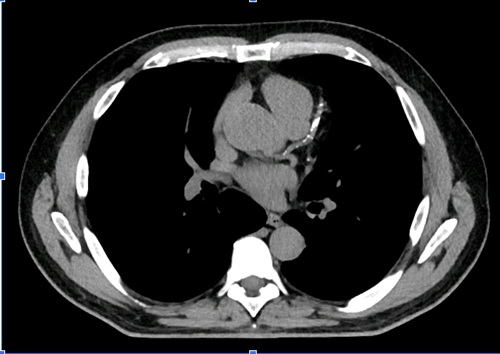

Tomografia de tòrax sense contrast on es detecta calcificació extensa a les artèries coronàries

Segons els resultats, a les persones que han patit un esdeveniment cardiovascular, el fet de tenir una quantitat elevada d'aquesta lipoproteïna a la sang s'associa amb una probabilitat un 40% més gran de patir malaltia coronària multivas. Un fet que també es produeix a aquells pacients sense símptomes cardíacs però amb atrterioesclerosi, que presenten nivells elevats, similars a aquells que ja han patit un accident cardiovascular. A més, les persones que en presenten més a la seva sang, també tenen nivells més elevats de calci en aquests vasos sanguinis, un altre clar indicador de risc cardíac.